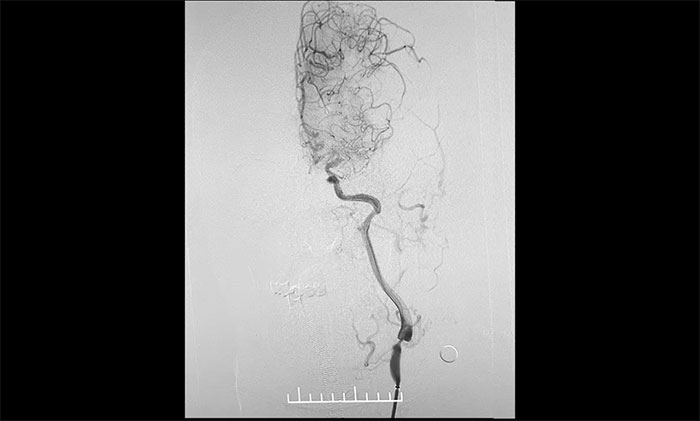

入院后,脑血管造影检查确诊:左颈内动脉海绵窦段、床突段多发动脉瘤,同时左颈内动脉起始段重度狭窄,眼动脉段狭窄,左大脑中动脉M1段闭塞。席刚明教授指出,从治疗的原则上这两种疾病是相互排斥的,血管狭窄的治疗需要进行单抗甚至双抗的一级卒中预防,也就是抗血小板治疗;而动脉瘤的治疗不能进行抗血小板治疗,因为一旦动脉瘤破裂,之前的抗血小板治疗会起到相反的作用,造成出血增加,所以治疗便成了一个“复杂”而又“棘手”的问题。

术中,席刚明教授、王贵平博士先对左颈内动脉起始段重度狭窄处进行开通治疗,在保护伞下经过多次球囊扩张后,顺利释放支架于左颈内动脉起始段至左颈总动脉末段,造影见狭窄明显改善,顺利开通血管。

术中,席刚明教授、王贵平博士克服血管迂曲困难,经过多次尝试,多次球囊扩张、“按摩”后,最终顺利释放密网支架至左颈内动脉眼动脉段、左颈内动脉床突段、左颈内动脉海绵窦段。造影及3D造影见,动脉瘤瘤内造影剂明显滞留,左颈内动脉、左大脑前动脉显影可,载瘤动脉通畅,获得了理想的血管重建。复查造影,左颈总动脉造影见左颈总动脉、左颈内动脉、左大脑前动脉显影可。CT见支架打开贴壁满意,XperCT未见颅内出血,手术圆满完成,顺利拆除“不定时炸弹”并打通大脑生命线。

▲ 颈动脉重度狭窄解除,打通大脑生命线